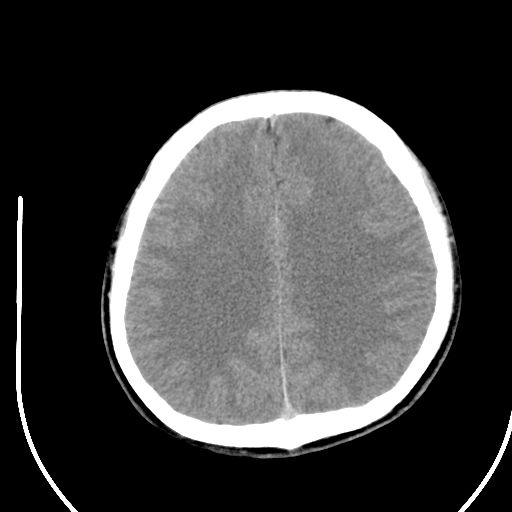

标题: CT28158:男,27Y。头痛数月,左顶叶血管瘤。 [打印本页]

标题: CT28158:男,27Y。头痛数月,左顶叶血管瘤。